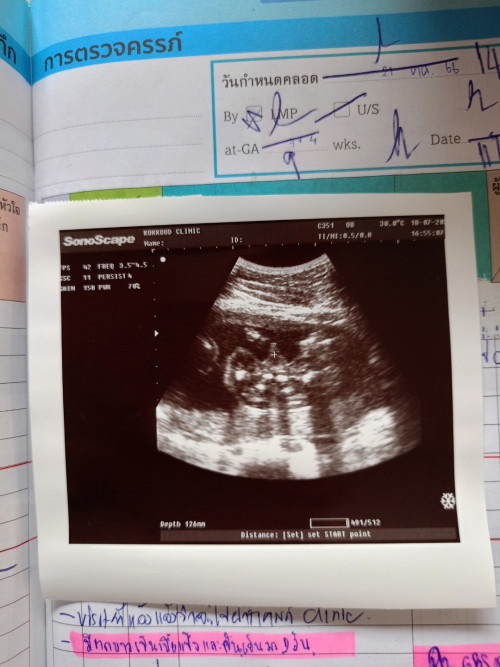

สอบถามรูปอัลตราซาวน์ค่ะ

คุณหมอบอกได้ผู้ชาย จู๋โผล่ คุณเเม่ว่าชัวร์มั้ยคะ ขอดูรูปอัลตราซาวน์เเม่ๆที่ได้ลูกผู้ชายหน่อยค่า

บ้านนี้ชายทั้งแท่งเลยค่ะ

หมอบอกชายเหมือนกันค่ะ

บ้านนี้หมอบอกได้ผช.จ้า

บ้านนี้ก็ลูกชายจ้า

บ้านนี้เป็นชายจ้า

บ้านนี้ชัดเจนมากค่ะ

หมอบอกชาย100%